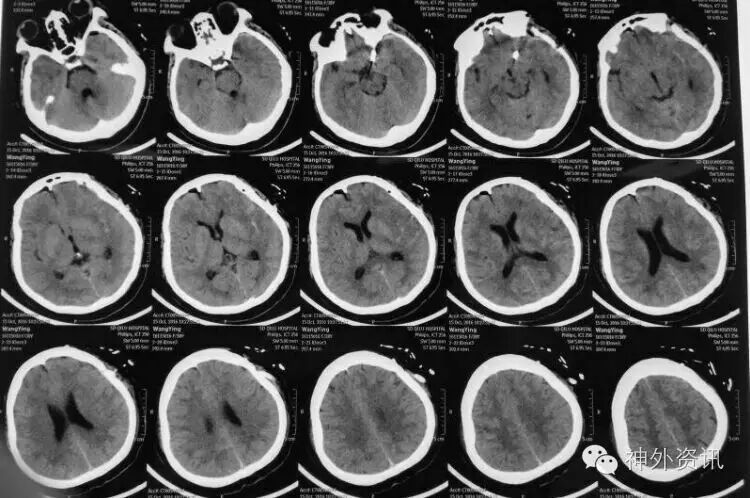

患者青年女性,3天前突发头痛伴恶心、呕吐入院。无阳性病史。Hunt一Hess分级I级。CT示SAH,左鞍上池、侧裂根部出血较多!

术后影像

术后cT未見术区缺血,病人语言、肢体活动正常!